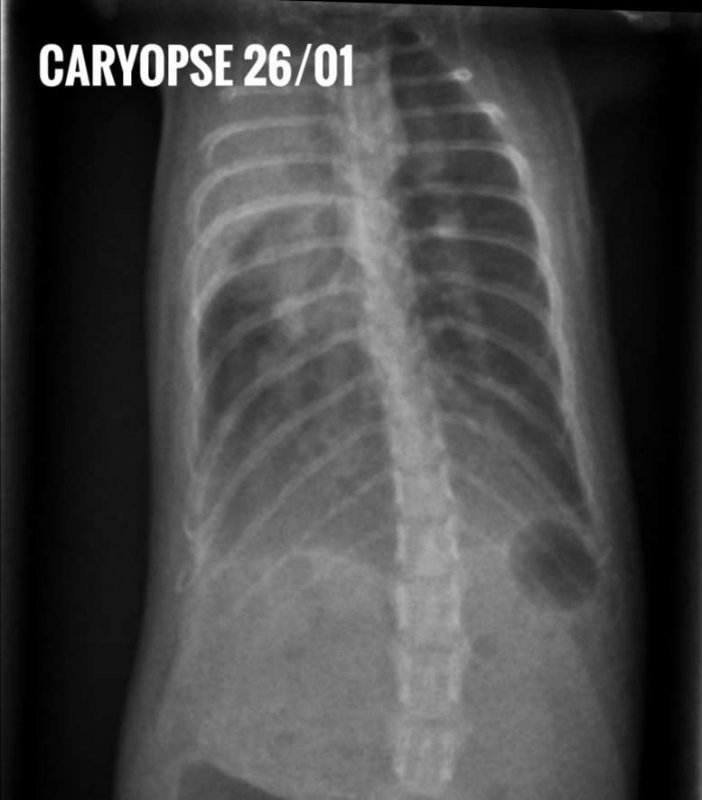

Le 12 janvier : revisite véto. Caryopse est vraiment inquiétant, les mâles de manière générale sont bien plus touchés avec 3 bébés qui présentent des bruits pulmonaires à l'auscultation. On décide de faire une radio pour Caryopse, afin d'avoir un comparatif possible et voir l'évolution. La radio est vraiment moche, je suis atterrée de voir ses poumons comme ça mais bon, on fait ce qu'on peut... On arrête l'enroflox... et on ajoute de l'azythromycine. On fait également un prélévement nasal chez Pyridion qui est celui qui a le nez le plus encombré des garçons. Je sais qu'il y a deux antibiotiques en cours, mais je me dis que s'il y a ne serait-ce qu'une petite change d'identifier clairement ce qu'ils ont, je prends.

-Caryopse, l'ancien plus touché que nous avions radiographié, nous refaisons une radio -> Il y a une amélioration, encore une bonne marge de progrès certes, mais ça va mieux ;

J'ai mis les radios de Drupe du 26/01, et les deux radios de Caryopse, pour ceux qui seraient curieux. Idem, j'ajoute les courbes de poids, j'ai un suivi au jour le jour, des fois que ça intéresse des gens (si vous voulez que j'enlève les noms de médocs dessus pour plutôt mettre les noms de molécules, je peux, pas de soucis).

-les radios de Caryopse ce vendredi montrent encore une légère amélioration, le côté gauche semble sain, le droit encore touché. Ça correspond au fait qu'il est physiquement mieux ;